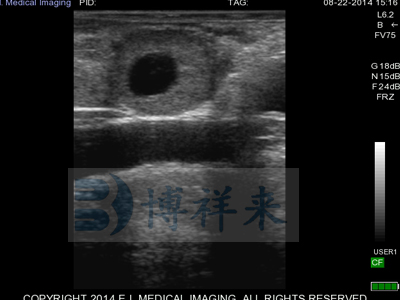

L7HD 高频线阵直肠探头(5-9MHZ可变) 高清分辨率

适用对象:牛马骆驼等大动物生殖检查、肌腱检查、新生犊牛肺部检查。